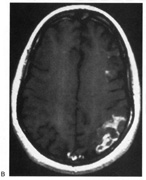

Fig. 5. Macula-splitting hemianopia. A 47-year-old man with AIDS and sudden onset of poor vision. A. Fields show complete left hemianopia. B. MRI shows lesion of right lateral occipital cortex, affecting distal optic radiations. Biopsy showed nonspecific encephalitis.

The optic radiation may be affected anywhere in its course (see Chapter 4); the type of visual field defect reflects the site of damage. Ischemic or hemorrhagic lesions of the internal capsule affect the optic radiation while it is still a relatively compact bundle, usually causing a complete homonymous hemianopia. A similar defect can arise from damage close to the termination in striate cortex (Fig. 5). Lesions of the ventral fibers in the anterior temporal lobe cause a contralateral superior visual quadrant defect (Fig. 6). Most often this defect aligns on the vertical meridian, with variable extension toward the horizontal meridian and central vision.33 Lesions of the dorsal fibers in the parietal lobe cause an inferior visual quadrant defect (Fig. 7). Because there is no sharp demarcation of the dorsal fibers from the ventral fibers in this portion of the posterior pathway, the defect seldom aligns along the horizontal meridian.33 Overall, quadrantanopia is more frequent with lesions of striate cortex.33 Lesions of the temporal lobe more than 8 cm posterior to its anterior tip can affect both upper and lower radiations. Small lesions also may affect certain portions of the radiations and spare others; for example, damage to the midportion of the optic radiation can mimic the sectoranopias of LGN lesions (Fig. 8).34 Although there can be some incongruity to the visual field defects of optic radiation lesions, this is less marked than the incongruity with optic tract lesions.